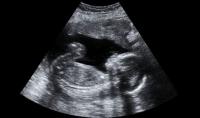

Mit mutat az ultrahang?

Az egyik legizgatottabban várt vizsgálat a gyermekvárás hónapjai alatt az ultrahang. Ennek a vizsgálatnak nemcsak komoly diagnosztikai jelentősége van, de betekintést nyújt a növekvő, várva-várt kicsi világába is, még akkor is,... »